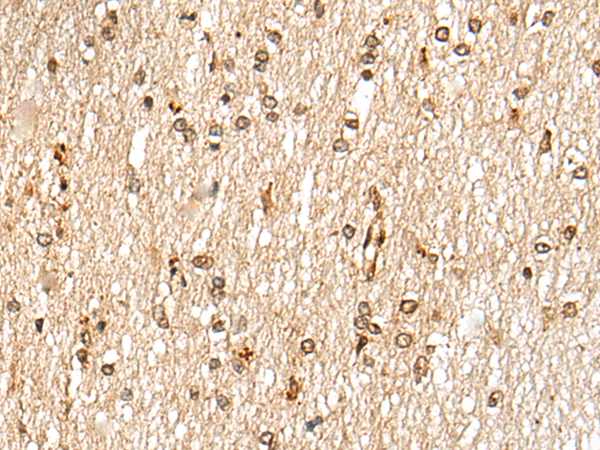

The image is immunohistochemistry of paraffin-embedded Human brain tissue using P12940(NKX3-2 Antibody) at dilution 1/25. (Original magnification: ×200) |